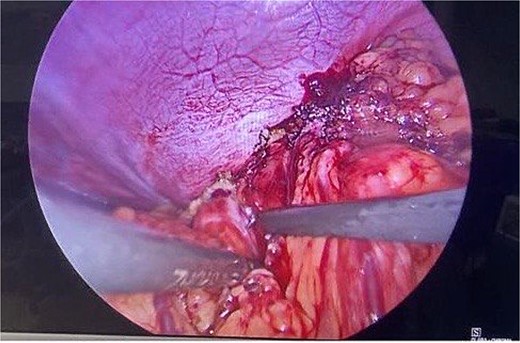

Routine examinations, including total blood counts, differential blood counts, renal function tests, and liver function tests, were within normal limits. The chest X-ray PA view showed the herniation of bowel loops into the left hemithorax with the collapse of the lower zone of the lung with no evidence of previous fracture (Fig. 1). Computed tomography (CT) showed a defect of size around 4 cm with evidence of protrusion of intra-abdominal content in the left hemidiaphragm with basal atelectasis of the left lung and mild dilatation of the jejunal bowel loops with a few air-fluid levels without a transition point (Fig. 2). The patient underwent laparoscopic left diaphragmatic hernia repair with mesh hernioplasty after 6 h of admission. The intraoperative findings revealed a defect of size 4 cm × 2 cm at the posterolateral aspect of the left hemidiaphragm with protrusion of the transverse colon, omentum, and part of the spleen with adhesions (Fig. 3). The content of the hernia was reduced, and primary repair of the defect was done (Fig. 4), and the defect was closed with a 10 × 15 cm intraperitoneal onlay composite mesh (Fig. 5). A postoperative X-ray showed no evidence of herniation of the bowel loops above the left hemidiaphragm (Fig. 6). He was discharged on the fourth postoperative day with oral medications. Follow-up in the outpatient department on the 14th postoperative day showed that he was doing well.

Intraoperative picture following reduction of hernia. The defect is being closed with prolene.